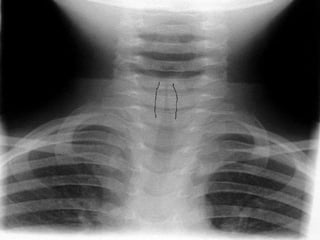

Radiografías…?

• No son de uso rutinario

•Radiografía AP de cuello 50% de lospacientes

muestran el signo clásico de aguja o torre

•Disminución de la columna de aire subglótico y

en la proyección lateral la presencia de

sobredistención de hipofaringe

Radiografías…? Children and Infants– Acute Management of Croup. August 2010 disponible en http://www0.health.nsw.gov.au/policies/pd/2010/pdf/PD2010_053.pdf • No son de uso rutinario •Radiografía AP de cuello 50% de lospacientes muestran el signo clásico de aguja o torre •Disminución de la columna de aire subglótico y en la proyección lateral la presencia de sobredistención de hipofaringe • La BH no es útil